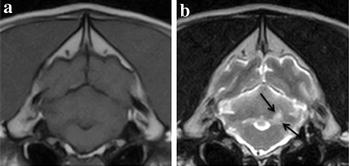

Fig. 2.

Lacunar infarct classified as limited. Brain magnetic resonance imaging (MRI) of an 8-year-old female neutered labrador retriever obtained within 48 h after onset of neurological deficits. Arrows indicate the cerebellar region affected by the ischaemic stroke. a Transverse plane T1-weighted at the level of the rostral cerebellum, b transverse plane T2-weighted at the level of the rostral cerebellum

Images obtained by a 0.4T MRI unit (Aperto Permanent Magnet, Hitachi)

The median time from onset of clinical signs to MR exam was 1 day. In all dogs, a single cerebellar infarct was identified. All infarcts were located to the rostral and tentorial part of the cerebellum in the territory of the RCeA (right n = 10, left n = 11, midline n = 2), with 19/23 infarcts being territorial and wedge-shaped and 4/23 infarcts being lacunar with a suspected occlusion of a deep penetrating artery from the RCeA resulting in ovoid lesions of the central part of the cerebellum. No significant mass effect or contrast enhancement was seen with any of the lesions (Figs. 1, 2). In addition to conventional MRI, gradient echo imaging, diffusion weighted imaging, and magnetic resonance angiography were performed in 13, 3, and 1 dog, respectively. The lesion appeared hyperintense on gradient echo and diffusion weighted images, and angiography revealed no signs of occlusive disease or vascular malformations. CSF analysis was performed in 10 dogs with unremarkable findings.